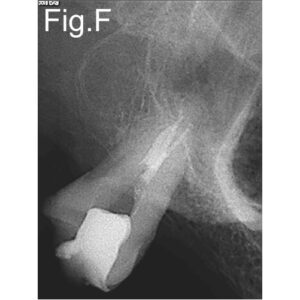

- Preoperative radiological assessment: mesial decay

Pre-operative periapical radiographs in different angulations or tomography favour the establishment of a correct treatment plan. In this particular case the distal buccal canal was out of its normal position making it difficult to find the entrance. Although under microscope visualization we had to follow root fusion line to find the canal. It was near the palatal. The ultrasonic tips were very important to reach the distal buccal canal at this stage. Another important factor was the common entrance of the two channels, which made difficult both a correct approach and the obturation. Clinicians should be aware of this anatomical conformation before starting the treatment. A straight irrigation protocol is imperative in this these cases. Only experience and knowledge can avoid errors that may be irreversible.